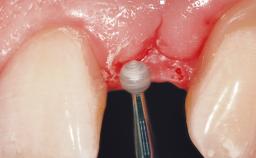

The video demonstrates implant placement using a surgical stent according to the principle of prosthodontically driven implant placement. The deficient ridge is augmented with locally harvested autologous bone chips, a superficial layer of xenogenic DBBM particles and a resorbable collagen membrane. The surgery is completed with a precise, tension-free primary wound closure.

The case concludes with the presentation of the final prosthesis and the esthetic outcome, demonstrating stable soft tissue conditions and stable bone crest levels at the 3-year follow-up.

Soft Tissue Contour and Volume Slightly compromised